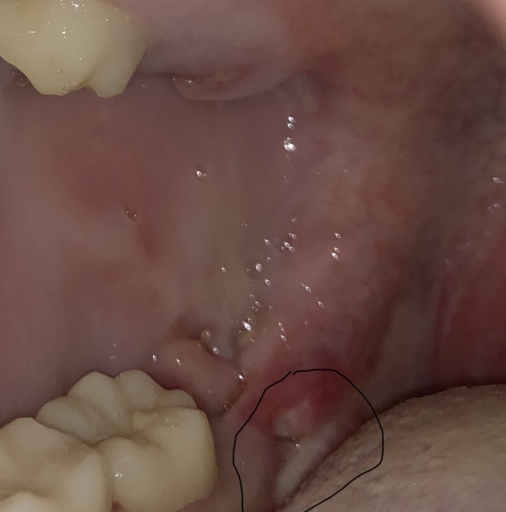

Hi, I have a frenulum on the right side of my mouth. It connects to my gums about 1cm behind the upper and lower back molars. It has become tight and painful. Have you ever seen anything like this? Is it safe to have it cut? I will attempt to add a photo. Thank you, H. Jay Graber

A frenum or frenulum is a small fold of tissue that restricts and secures the motion of a mobile organ. I have not heard of a frenulum in the back of the mouth. It would be best to bring this to the attention of your dentist, especially because it is causing discomfort. I did not see a picture attached to your question, however I am wondering if it is part of your cheek or possibly an impacted tooth that may be causing this discomfort. Use warm salt water rinses several times a day to soothe the tissues until you have a proper exam and diagnosis.

A frenulum or frenum is a small fold of tissue that restricts or secures the motion of a mobile organ. I have not seen a fold of tissue (unless sutured) that connects distal to the molars. There is a frenum that connects your tongue to the floor of your mouth as well as one that attaches your lips to your jaws. Since you are experiencing pain, it is important for you to see your dentist immediately to be sure you do not have an infection or a tooth that is creating swelling in the area.